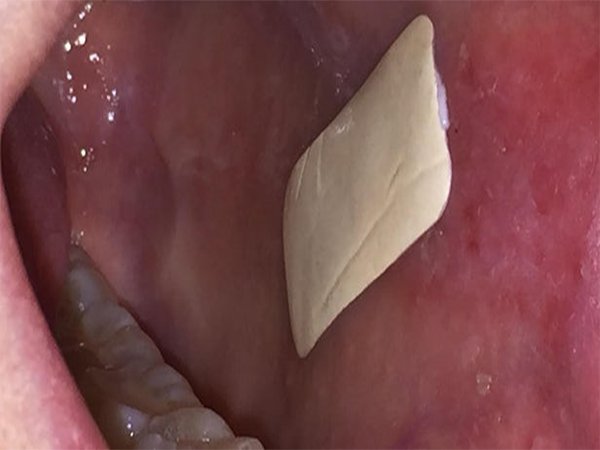

تهران – ایرنا – محققان دانشگاه شفیلد انگلیس بانداژ جدیدی را ساختند که به درون دهان می چسبد و با رهاسازی دارو عوارضی مانند آفت و لیکن پلان دهان را بهبود می بخشد.به گزارش گروه علمی ایرنا از از پایگاه خبری مدیکال ساینس،معمولا برای درمان آفت، لیکن پلان دهان (یا خزه پوستی یک بیماری التهابی نسبتا شایع پوست و مخاط است) و سایر بیماری هایی که موجب جراحت دهان می شوند، از کرم ها یا پمادهای استروییدی یا دهان شویه استفاده می شود. اما این مواد به محض استفاده در تمام دهان پخش شده و مدت زمان تماس آن ها با محل زخم کاهش می یابد. در نتیجه درمان مطلوب حاصل نمی شود. اما اکنون محققان بانداژی را ساختند که مانع از پخش شدن دارو در دهان می شود و آن را مستقیما روی زخم رها می کند. این بانداژ با استفاده از الیاف پلیمری آغشته به استروییدی موسوم به clobetasol-17-propionate تولید شده است.یک طرف این بانداژ توسط لایه ای از چسب زیستی غیرسمی و بسیار انعطاف پذیر و طرف دیگر آن توسط یک لایه نفوذناپذیر پوشیده شده است. این ساختار امکان چسبیدن طولانی بانداژ به دهان کاربر و رهاسازی داروی استروییدی را روی زخم فراهم می کند اما مانع پخش شدن دارو در دهان می شود. در آزمایشات اولیه که با کمک ۲۶ داوطلب انجام شد، این بانداژ به مدت ۲ ساعت در دهان داوطلبان باقی ماند و دارو را در محل زخم آزاد کرد. قرار است به زودی آزمایشات بالینی این بانداژ در چندین کلینیک در انگلیس و آمریکا آغاز شود. گزارش کامل این تحقیقات در نشریه Biomaterials منتشر شده است.